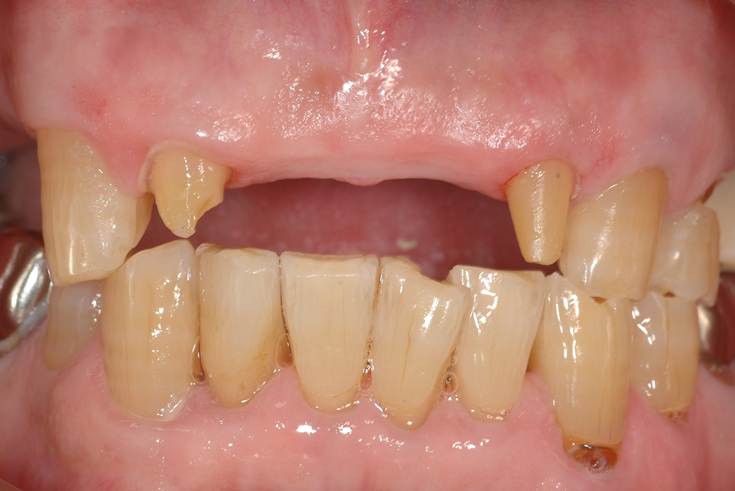

左が術前写真です。歯茎が痩せていて虫歯になっています。こういう場合、単に削って白い樹脂を詰めるでしょうか?

このケースのように歯茎が薄い場合(付着歯肉の厚みがなく狭い)、白い樹脂を詰めてもまた歯茎が痩せていくことが予想されます。

右は、術後写真ですが、白い樹脂は詰めていません。歯茎を作って、虫歯の部分を完全に覆いました。

術前→9日後→3週間→5周後→1年2ヶ月後です。5週後で少し歯茎が退縮しますが、その後歯茎が成熟し厚みも増して「クリーピング」が起こって虫歯の部分を完全に歯茎で覆うことが出来ました。縦切開を入れていないので術後も綺麗です。